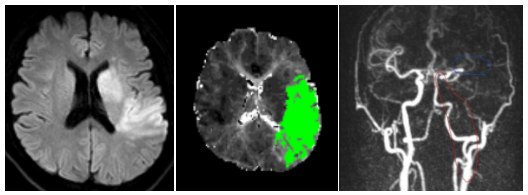

綜合《揚子晚報》等內地媒體報道,35歲王先生因突然出現了口角歪斜、言語不能、右側偏癱等癥狀,隨即報警,被送到南京市第一醫院就醫,確診急性缺血性腦梗死,原因是王先生腦內左側頸動脈和左側大腦中動脈發生了堵塞。

南京一名35歲男子不吸煙不喝酒,不過他經常在運動後,用按摩槍按摩身體放鬆肌肉。(示意圖。網上圖片) 王先生確診急性缺血性腦梗死。(微博) 王先生確診急性缺血性腦梗死。(微博)

接診的侯建康醫生指出,頸動脈位置表淺,如果持續受外力刺激及損傷,如頸部按摩、快速劇烈轉頸、舉重、瑜伽等,在特定情況下有可能形成動脈夾層。王先生的頸動脈夾層大概率是因為使用按摩槍按摩頸部過猛、過頻所致。侯醫生提醒,頸部按摩一定要謹慎,切忌用力過猛、頻率過高。慶幸王先生在手術後已康復出院